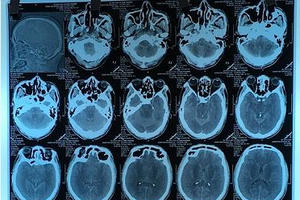

Theo thông tin mới nhất, một trong số bệnh nhân được cứu sống trong vụ 3 người chết nghi ngộ độc rượu ở Nam Giang (Quảng Nam) có nguy cơ mù mắt.

Theo thông tin từ Bệnh viện Bạch Mai, mới đây BV đã tiếp nhận một bệnh nhân ngộ độc methanol rất nặng do uống cồn thay rượu.